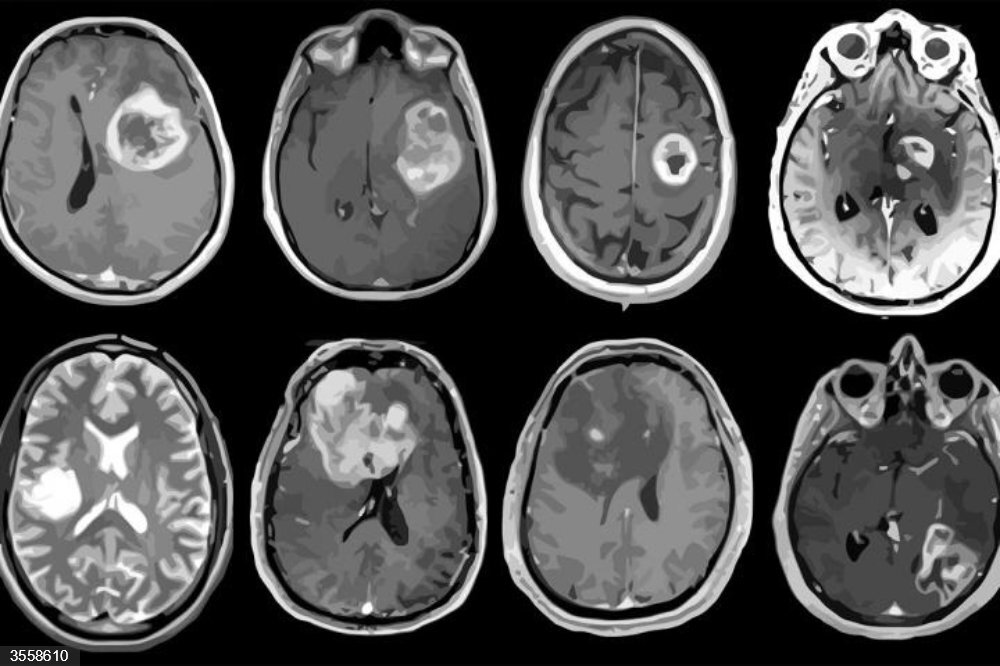

Glioblastoma, tumor cerebral agresivo. / Fuente: Europa Press

El glioblastoma es un tumor cerebral de grado 4 que representa cerca del 50 % de los tumores cerebrales agresivos. Su incidencia es de unos tres casos por cada 100.000 habitantes, lo que se traduce en aproximadamente 1.500 nuevos diagnósticos al año en España.